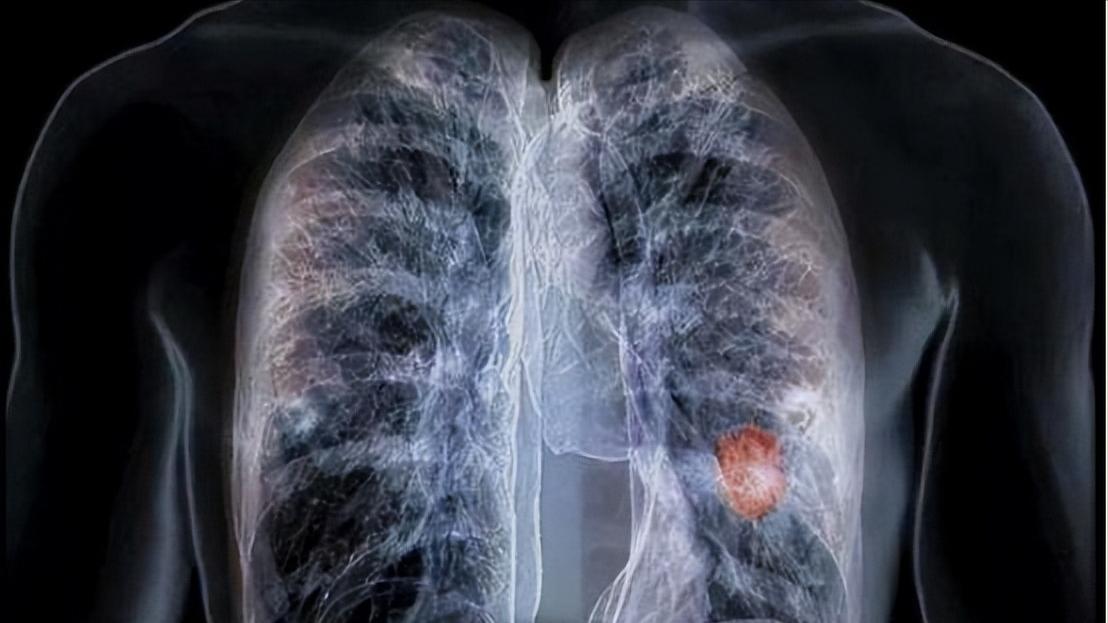

王女士之所以这么担惊受怕,其实是受到身边人患癌的影响,不可否认,癌症的发生率和死亡率的确不容小觑。据一项调查显示,肺癌已经是我国最高发的癌症,每年的都有将近70万人患癌,并且肺癌的发病率和死亡率都位居首位。

但必须要知道的是,80%~90%的肺结节都是良性的,肺部出现结节不一定是由肺癌引起,也可能是其他疾病造成的,例如肺炎、肺结核,也可能是以前肺结核留下的疤,真正是肺癌的比例非常小。

尤其是肺部小结节,它大部分是由良性疾病引起的,对于小于6毫米的肺结节,肺癌的概率甚至不到1%,但有人可能会说:“我的肺结节比较大,肯定就是癌症”。

那你可能不知道,直径在6~8毫米之间的肺结节,患肺癌的概率甚至只有0.5%~2%,因此并不需要过于担心。